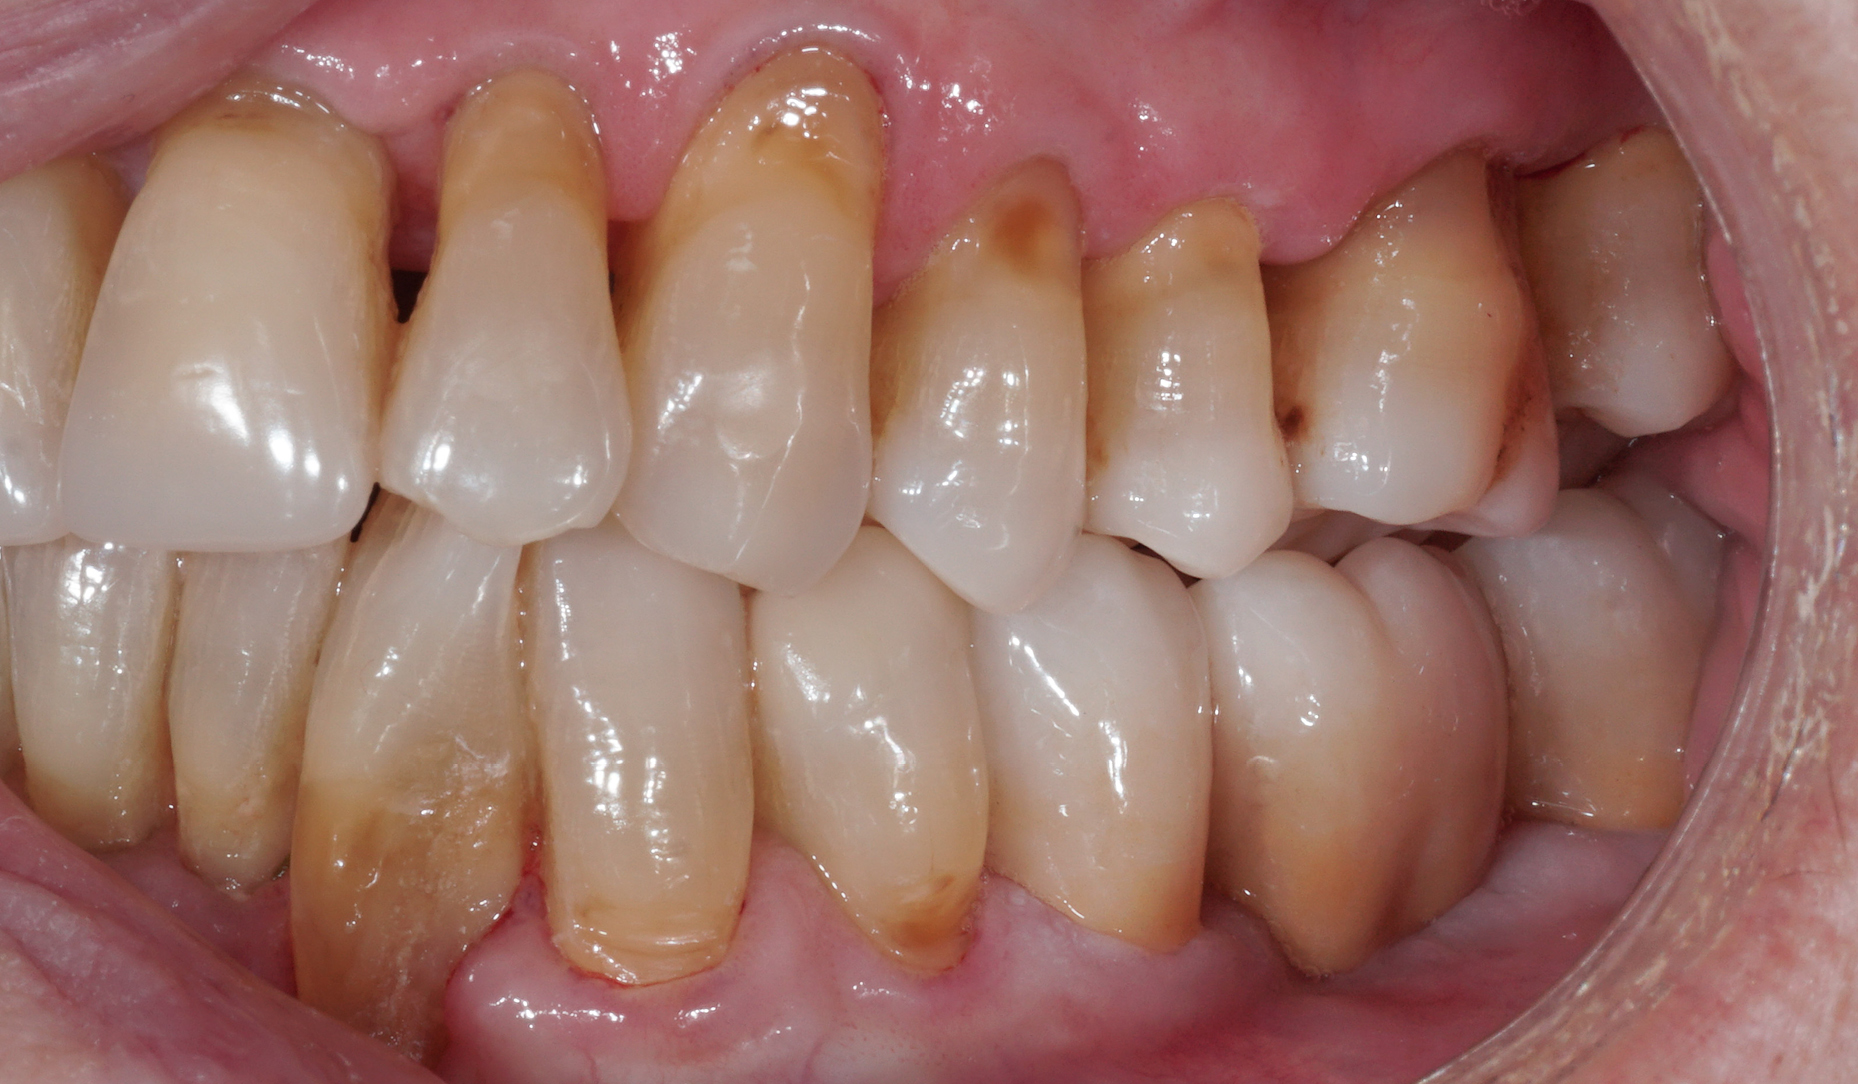

Ryc. 1. Stan przed leczeniem po złożonym złamaniu żuchwy – dyskluzja po lewej stronie.

Ryc. 2. Stan kliniczny podczas pierwszej wizyty wgabinecie stomatologicznym.

Ryc. 3. Zgryz otwarty w lewym, tylnym obszarze żuchwy.

Ryc. 11. Stan kliniczny po odbudowie zębów za pomocą nakładu z dwukrzemianu litu i mostu z tlenku cyrkonu KATANA™.

Ryc. 12. Nakład onlay i most na swoim miejscu w jamie ustnej (po adhezyjnym osadzeniu na PANAVIATM V5 i samoadhezyjnym cementowaniu na PANAVIATM SA Cement Universal).